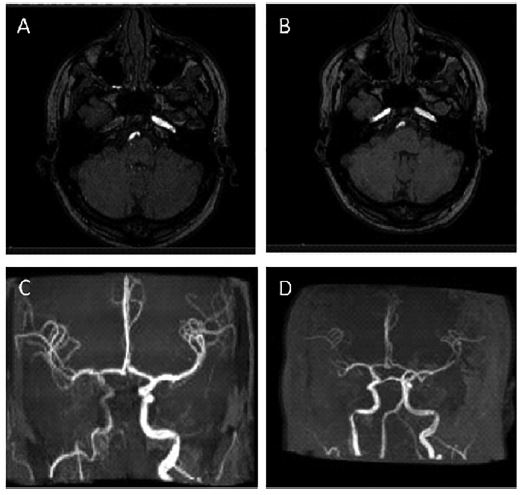

Síndrome del Arlequín como presentación inusual de la disección carotídea